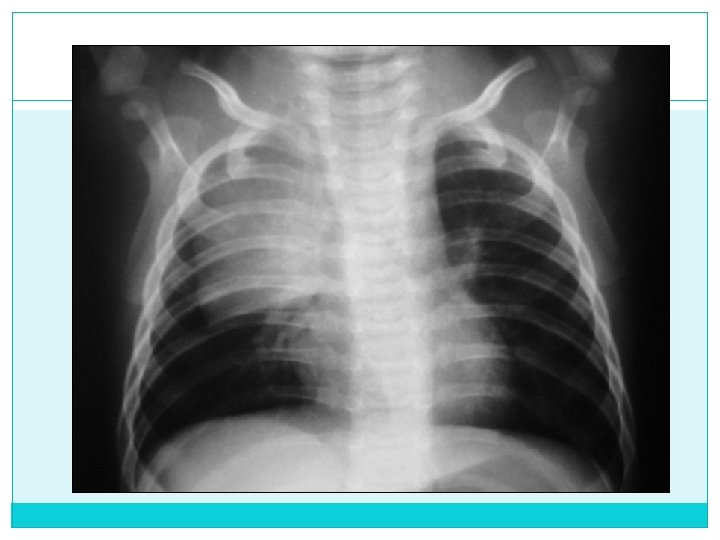

Contraste Es adecuado cuando se pueden diferenciar adecuadamente estructuras de densidad diferentes: partes blandas, pulmón y esqueleto Inspiración Cuando se pueden contar 8 a 9 arcos costales posteriores sobre el parenquima pulmonar o 6 arcos costales anteriores § Frontal: Contar arcos costales anteriores (cúpula es anterior) Bien inspirada: Cúpula a nivel del 6 to. arco Hiperinsuflación: Cúpula por debajo del 8 vo. arco Hipoinsuflación (espirada): Cúpula por encima 4 to. Arco

Bien Inspirada